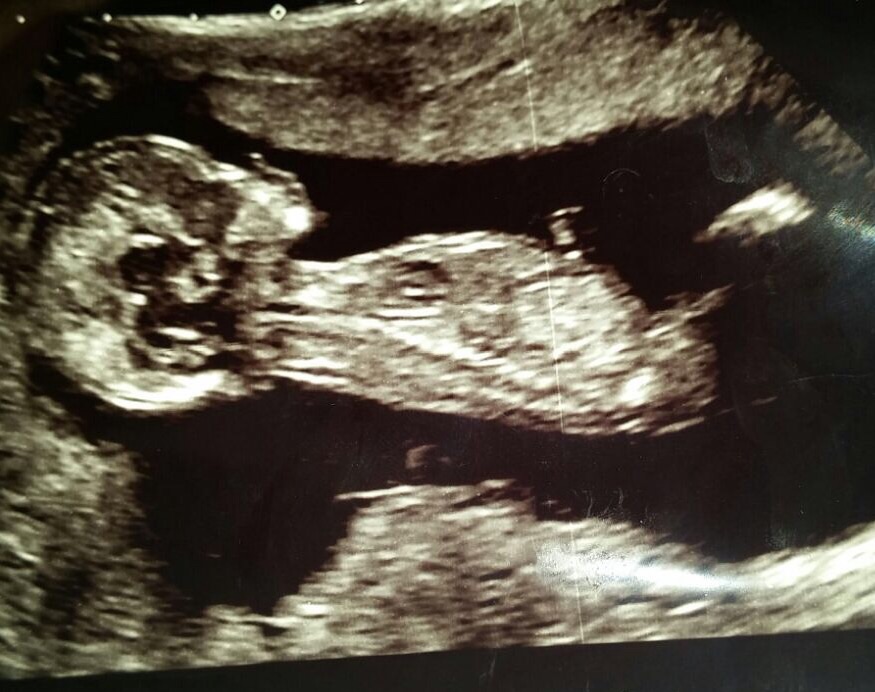

Any guesses 13.5-14 weeks